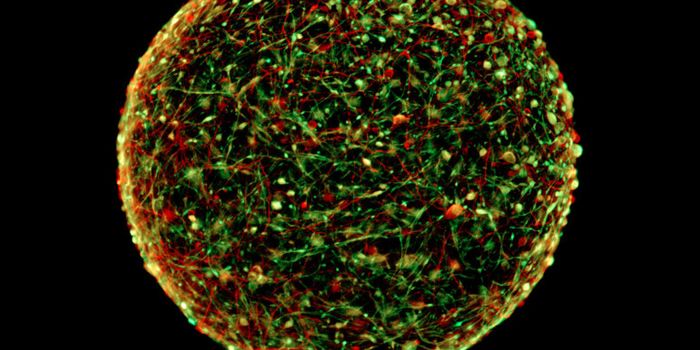

FEB 21, 2023Cell & Molecular BiologyThe Griffith Lab at UNC discovered telomeric protein & potential biomarker VR (green), shown in the nuclei (blue) of hum ...

MAR 08, 2016ImmunologyScientists have grown tiny, barely visible “mini-brains.” These balls of neurons and other human cells mimic ...